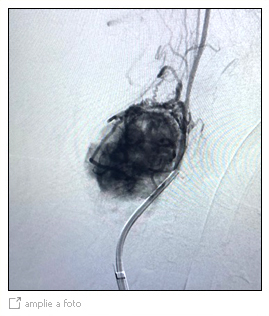

Embolização pre-operatória de tumor do glomus carotídeo